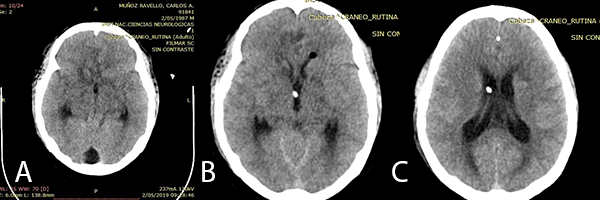

Paciente refiere que aproximadamente un mes y medio antes del ingreso inició cefalea holocraneana punzante de intensidad 2/10 que fue progresando hasta intensidad 6/10 que duraba 3 horas aproximadamente y cedía con el descanso (paciente asoció dicha cefalea a estrés). Al persistir los síntomas, el paciente se auto medica con analgésicos (no recuerda el nombre) pero no hubo mejoría clínica. Una semana antes del ingreso refiere que la cefalea se incrementa al realizar esfuerzo físico llegando hasta 9/10 de intensidad. Dos días antes del ingreso, el paciente presenta vómitos matutinos en dos oportunidades, además de visión borrosa con aparente adormecimiento de la mano derecha, con un episodio de afasia de 10 segundos de duración sin compromiso de conciencia. Es llevado a clínica particular donde realizan una Resonancia Magnética (RMN) contrastada (Imagen 1) e indican que sea referido a un establecimiento especializado por lo que acude al Instituto Nacional de Ciencias Neurológicas.

Imagen 1: RMN de cerebro: (A) y (B): cortes coronales en secuencia T1 con contraste donde se observan imágenes múltiples con captación de contraste en anillo. (C): corte axial en secuencia Flair que muestra edema peri lesional.

En el examen físico de ingreso, el paciente se encontraba en buen estado general, buen estado de hidratación, ventilando espontáneamente, Glasgow 15/15, pupilas isocóricas, fotorreactivas, sin déficit motor ni sensitivo, agudeza visual disminuida en ojo izquierdo. Inicialmente por la Resonancia Magnética (imagen 1), se sospechó de toxoplasmosis, recibiendo tratamiento médico, pero al no haber mejoría clínica es programado a biopsia por estereotaxia.

Las imágenes iniciales del paciente mostraron lesiones difusas. La secuencia T1 con contraste de la RMN mostró múltiples tuberculomas supra e infra tentoriales con un anillo que realza el contraste. Además en la secuencia Flair se evidenció edema perilesional de los tuberculomas. Sanei et al.(9) refieren que imagenológicamente la TBC en el SNC puede simular diferentes afecciones neurológicas (infecciosas y no infecciosas).